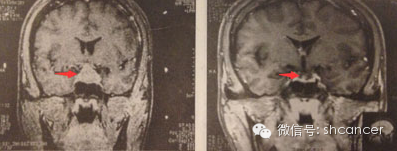

案例一:患者女,30岁,PRL垂体瘤,治疗前患者有疼痛、头晕、泌乳、闭经、不孕,用伽玛刀治疗后14个月复查,肿瘤消失。临床症状改善。目前患者已经怀孕。